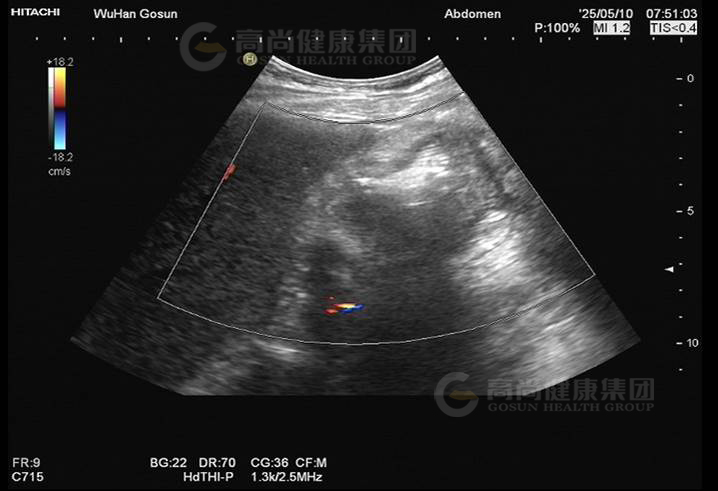

· 超声图像

图2-肝肾间隙包块

图3-肝肾间隙包块

图4-肝肾间隙包块

超声表现及意见:

肝肾间隙可见不均质包块,大小约7.5×6.5×5.2cm,界欠清,轮廓欠规整,壁厚,部分切面周边见高回声晕,内回声不均匀,呈假肾征,包块内部及周边血流信号不明显。

超声提示:

肝肾间隙不均质包块,考虑结肠或腹膜来源,建议进一步检查。